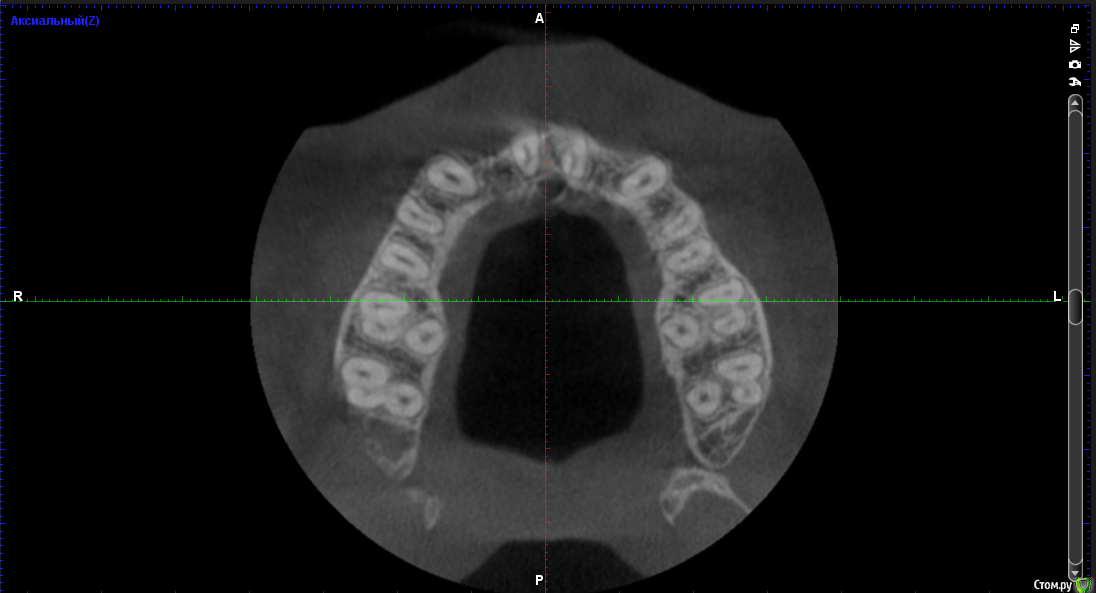

Тимур86 Опубликовано 22 сентября, 2016 Поделиться Опубликовано 22 сентября, 2016 Пациентка на ортодонтическом лечении.Нуждается в имплантации 12,22.В другой клинике предложили удалить 11 и 21 с костной пластикой,т.к. вестибулярно в области 11 отсутствует кость....Планируется установка Astra 3.0 в области 12 и 22 с использованием хирургического шабона,подсадкой СДТ и установкой ФДМ,через неделю временные коронки.Вопросы:1)зачем удалять 11 и 21? 2)нужна ли НКР? 3)можно ставить времяшки через неделю,учитывая подсадку СДТ? Ссылка на комментарий